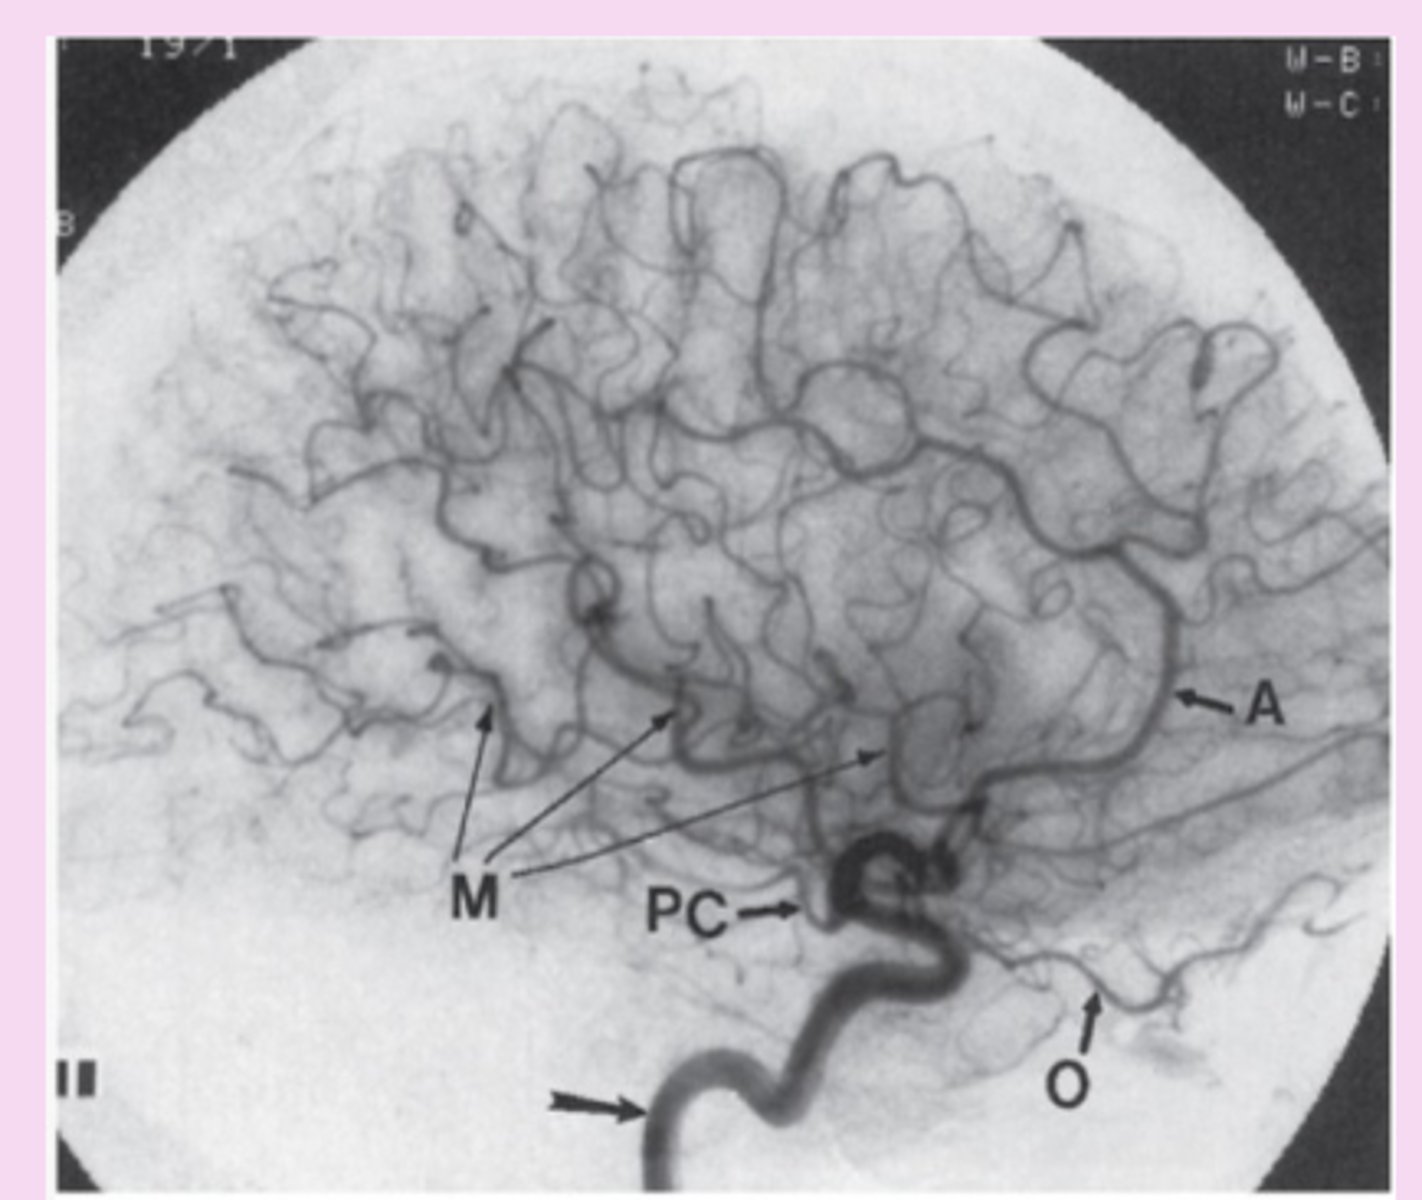

catheter-directed angiography

invasive, high risk procedure

small catheter in puncture of femoral artery > aorta > aortic arch > specific arteries > contrast material injected

gold standard= intracranial, extracranial, spinal vascular lesions